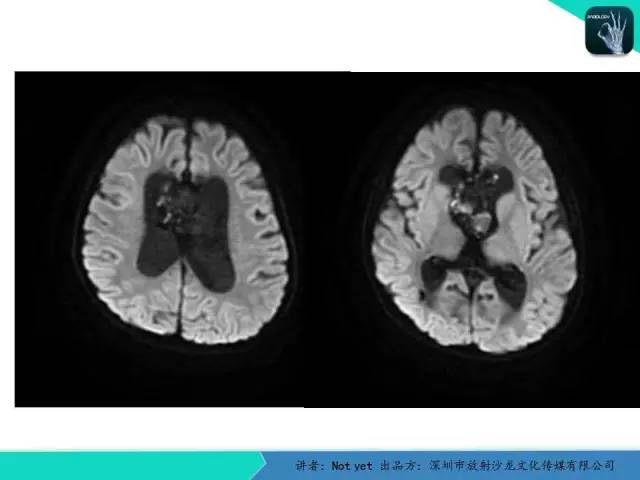

【病例】脑室内脉管瘤1例CT及MR影像诊断与鉴别